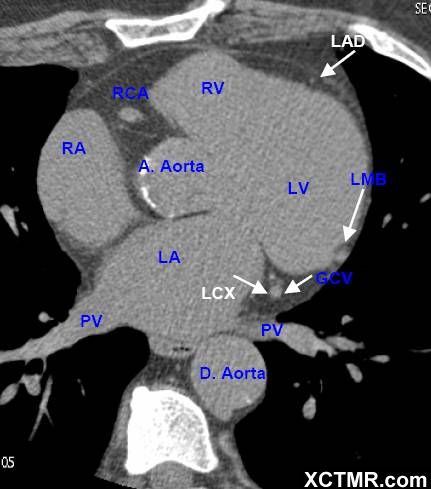

LA - Left Atrium 左心房

RA - Right Atrium 右心房

LV - Left Ventricle 左心室

RV - Right Ventricle 右心室

A. Aorta-Ascending Aorta 升主动脉

D. Aorta-Descending Aorta 降主动脉

PV - Pulmonary Vein 肺静脉

LAD - Left Anterior Descending Artery 左前降支

LCX - Left Circumflex Artery 左回旋支

LMB - Left Obtuse Marginal Branch 左边缘支(钝缘支)

GCV –Great Cardiac Vein 心大静脉